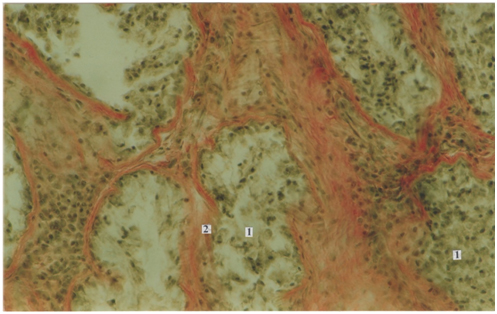

Статья имеет целью изучение железисто-лимфоидных взаимоотношений пищеварительного тракта в постнатальном онтогенезе и представляет особый интерес для клинической иммунологии. Макроскопическим и гистологическим методом нами исследованы слюнные железы, полученные от трупов 299 человек (язычные железы), начиная от новорожденных и до периода долгожительства, исследованы трупы представителей мужского и женского пола. Материал забирали в судебно-медицинских моргах Бюро СМЭ Департамента здравоохранения г. Москвы, что разрешено Постановлением Правительства РФ, Федеральный закон № 323, ст. 47, 4180-1, 355н. В фактический материал для исследования не включали случаи, когда при судебно-медицинском исследовании трупа выявляли патологические изменения пищеварительной системы. Микропрепараты (поперечные срезы) были окрашены гематоксилином-эозином и пикрофуксином по ван Гизону.

Малые слюнные железы, язычные и глоточные, располагаясь в толще языка и стенках глотки, выполняют важную эндокринную функцию – участвуют в обеспечении реакций местного иммунитета в ротовой полости. Множество публикаций посвящено регенеративным изменениям слизистой оболочки рта под действием секреторного иммуноглобулина А, который выполняет основную роль в регуляции местного иммунитета. В статье отражены важные аспекты возрастных изменений малых желез (язычных и глоточных). Характерная немногочисленность желез в детском возрасте обусловлена однотипностью питания в данном возрастном периоде, а снижение выработки секреторного иммуноглобулина А закономерно ведет к возникновению частых воспалительных процессов в полости рта и глотки. С возрастом устья желез расширяются и увеличивается их количество, что влечет за собой усиление местного иммунитета в ротовой полости и ротовой части глотки. Начиная с пожилого и старческого возраста наблюдаются инволютивные изменения, которые сопровождаются снижением выработки секреторного иммуноглобулина А и, соответственно, снижением показателей местного и гуморального иммунитета. Эти результаты полностью отражают топографические взаимоотношения желез с клетками лимфоидного ряда, и приведенные данные весьма актуальны для клинической иммунологии.